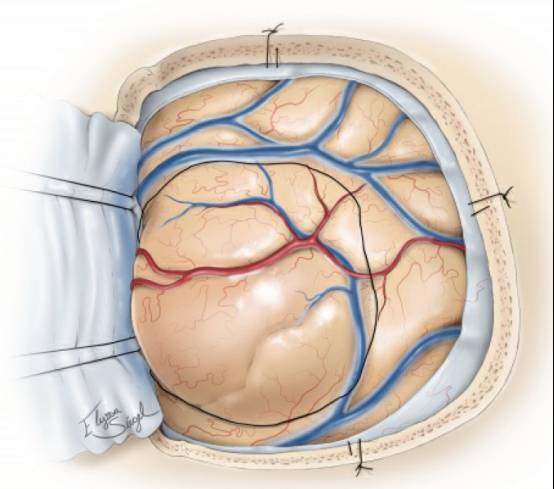

图7. 笔者常常借助肿瘤组织的一致性特点和术中导航环形离断肿瘤。如果可能的话尝试整块切除肿瘤。中央部分切除会导致导航精度会大大降低。更重要的是,整块切除肿瘤能够提高手术效率,减少失血,使操作者保持沿肿瘤边缘的平面将其切除。在肿瘤的内部和外围同时操作会导致肿瘤边缘混乱不清。.

吸引器可在术中可用于动态牵拉,以防止切除肿瘤后术腔的塌陷。

胶质瘤的白质剥离和分离技术值得特别重视。双极反复钳取并电凝肿瘤的假包膜,这种逐步的操作能够乳化假包膜并使其与瘤周的水肿组织分离。接下来,用吸引器吸除该乳化物,继续暴露下一层假包膜并进一步电凝和分离。

该技术将分离和电凝同步完成。换言之,是将双极电凝当成肿瘤剪刀一样使用,

注意在双极电凝头端持续冲水。(上图,图7插图)。

肿瘤对双极电凝的反应与正常脑组织有很大的不同;这是另一个可以指导外科医生的重要参数。一些低级别胶质瘤具有更多的纤维化,而一些肿瘤比正常组织更胶质化。沿着瘤周区域辨别边界有时具有相当大的挑战性。

图8. 最后将肿瘤从深部离断并移除。然后使用导航评估切除程度。为了达到更好的效果,可以进一步切除腔壁组织。切除一直持续到在瘤腔壁各个方向出现干净的白质(明亮且有光泽)。肿瘤颜色常呈晦暗。低级别胶质瘤经常延伸到室管膜水平和进入侧脑室,术者应该确定移除了肿瘤的最深部分。